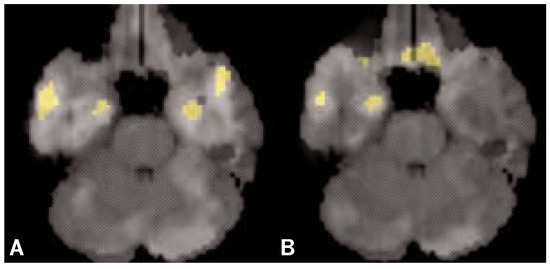

PET studies of memory

The publication of two discoveries [1, 2] set the ground for theories, experiments and clinical practice during the past 40 years in the neuroscience of memory. Since then, we know that memory is not supported by the total action of the entire brain but anatomically localizable like sensory and motor functions. It is the function of a neuronal network including both mediotemporal regions, particularly the hippocampal formations which were found to be indispensable for memory. Research with amnesic patients led to the next discovery that memory is not a unitary system but consists of at least five different subsystems which are subserved by different, though overlapping neuronal networks. In the following, the function of the “pioneer structure” hippocampus in the human was pinned down to episodic memory alone and became even further specified to learning/consolidation, novelty detection, deep processing, associative learning, and – not treated in this article – spatial learning.To further elucidate the function(s) of the hippocampal region in human memory we carried out two Positron Emission Tomography (PET) experiments testing the above hypotheses. The findings were straightforward: nothing challenged both hippocampal formations as much as establishing new semantic associations between previously unrelated words or pictures in memory. Full article

Figure 1